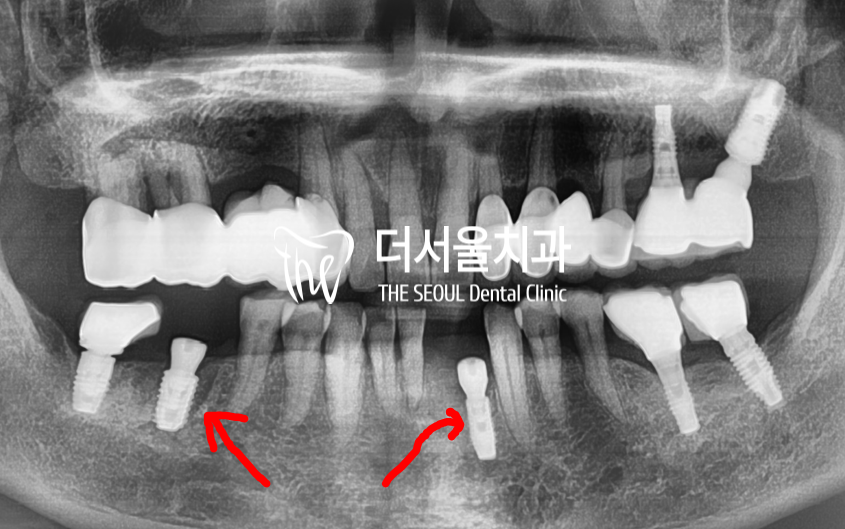

『2개월 소요』

하악이니, 뼈가 빨리 회복이 됩니다.

그래서 2개월 밖에 안 걸렸었습니다.

예측 했던 위치에 그대로 앞니 임플란트

및 어금니 임플란트를 심었으며

앞니 임플란트 의 경우에는

implant fixture 를 1개를 심어서

크라운 2개를 연결해드린 형태입니다.

비용절감도 되며,

또 아래 앞니들은 크기가 작기 때문에

임플란트 2개를 심기가 어렵거든요.

또 앞니들은 교합의 기능을

담당하지 않기 때문에

이렇게 만들어드리는게

더 환자 입장에서는

유리한 점들이 많습니다.^^